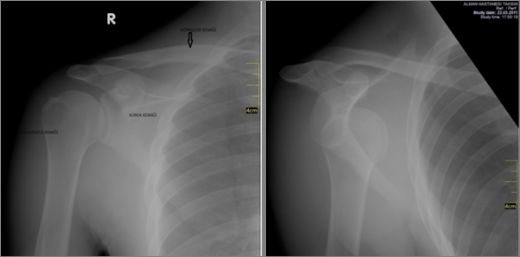

Omuz Kemikleri Özellikleri